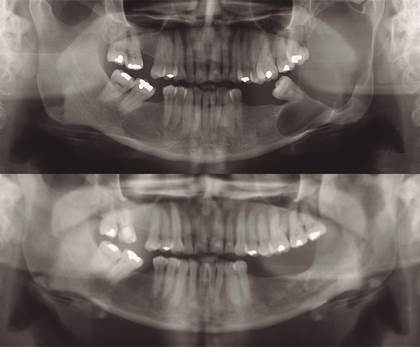

Paciente de sexo mujer, 42 años de edad, con antecedentes de hipotiroidismo en tratamiento, acude al Servicio de Cirugía Oral y Maxilofacial del Hospital San Juan de Dios, en Santiago de Chile, por aumento de volumen hemifacial izquierdo de 6 meses de evolución. Al examen clínico se observó un aumento de volumen de la región parotídea y submandibular izquierda (figura 1), desdentamiento parcial bimaxilar, abombamiento tablas óseas mandibulares y movilidad de tercer molar inferior izquierdo (diente 3.8) (figura 2). La radiografía panorámica reveló extensa lesión en zona posterior del cuerpo y en casi la totalidad de la rama mandibular izquierda, de características quísticas y expansivas, sugerentes de quiste odontogénico (figura 3). En la tomografía axial computarizada (TAC) se observó una lesión de aspecto quístico en la región mandibular izquierda, desde cuello condilar hasta cuerpo mandibular izquierdo, con expansión de corticales óseas vestibular y lingual (figura 4).

Seis meses después - al observar radiográficamente una disminución del área radiolúcida y aposición ósea (figura 5) - se realizó un nuevo abordaje, esta vez bajo anestesia general, para permitir un curetaje más agresivo y mayor remoción de tejido tumoral. Se realizó una nueva biopsia incisional y se aplicó solución de Carnoy. El resultado histopatológico fue ameloblastoma uniquístico patrón mural con proceso inflamatorio crónico y agudo.

La paciente se mantuvo en control clínico y radiográfico periódico, observándose disminución de la lesión y la aposición ósea mandibular, y la consecuente simetrización facial. Once meses posteriores a la primera intervención quirúrgica, se constató radiográficamente aposición ósea de la lesión radiolúcida del cuerpo y rama mandibular izquierda, límites netos esclerosados y expansión ósea a nivel de la rama mandibular (figura 6), aposición ósea que continúo progresivamente, como se observó en la radiografía panororámica realizada 21 meses postquirúrgica (figura 7).